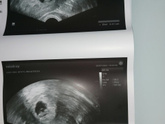

Девочки! Все отлично:малыш растёт, сердечко бьется???Я счастлива!!! По месячным срок 7,3.По узи 7 нед. На учёт встать до 3.08.Первый скрининг с 3.08 по 10.08.Отменяем с 13.07 эстрожель(дивигель) и дюфастон с 16.07.Утрик 3 раза … Читать далее